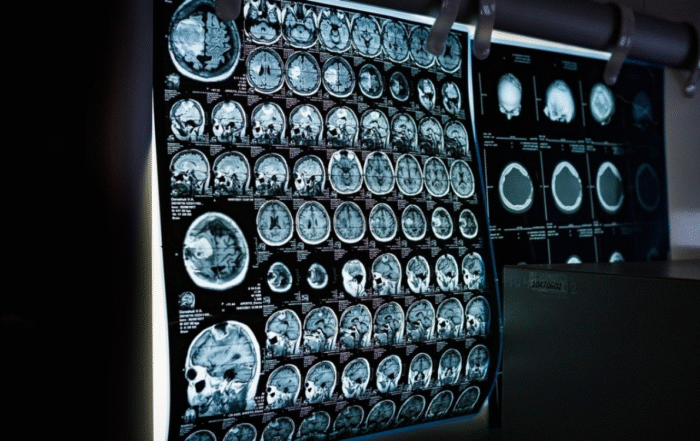

2010 marks another milestone: the launch of the first medical programme in Cyprus, which will be offered by St George’s, University of London in association with the University of Nicosia.